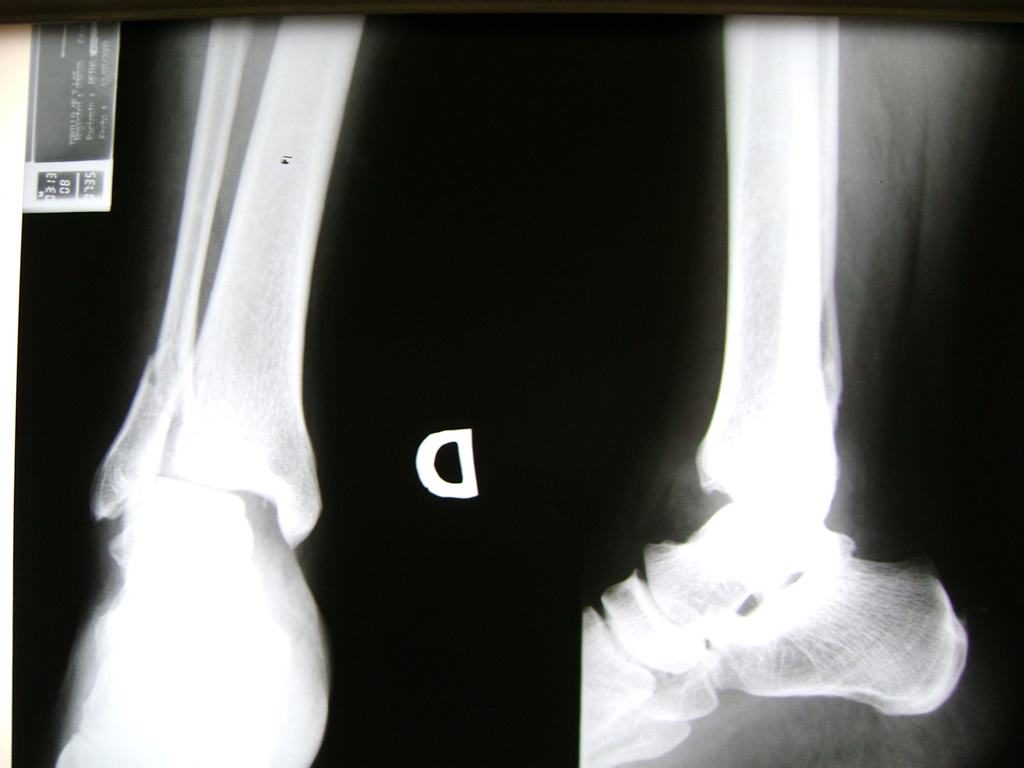

Una fractura de tobillo es la rotura de uno o más de los huesos del tobillo. Estas fracturas pueden ser:

- Completas (el hueso está perforado y está en 2 partes).

- Los extremos de los huesos están desalineados entre sí (desplazados).

- La fractura se extiende hasta la articulación del tobillo (fractura intra-articular).